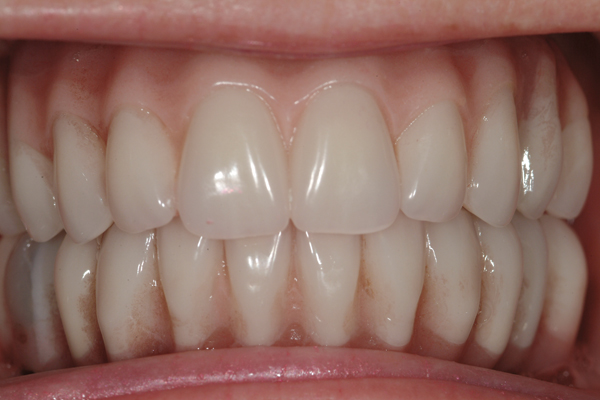

Dental rehabilitation with the All-on-4 treatment concept is often a life-changing event for edentulous and terminal dentition patients that results in unprecedented quality of life improvements (Figure 17 through Figure 20).

Fig 19. Patient smile shown 3 years post-treatment.

Figure 19

Fig 20. Patient intraoral condition 3 years following delivery of maxillary and mandibular All-on-4 definitive prosthesis.

Figure 20